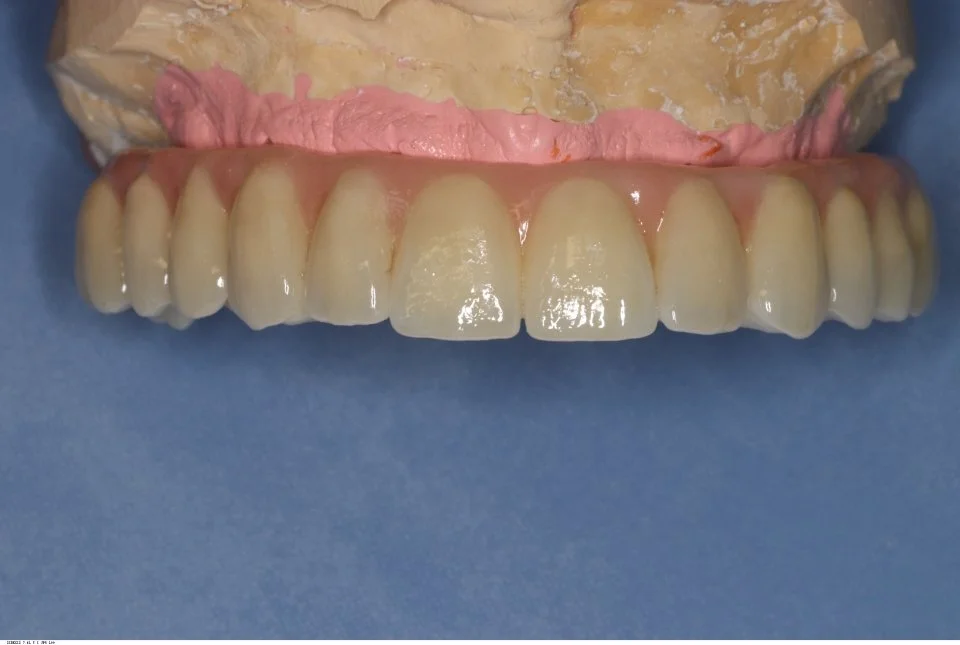

Following careful treatment planning discussion along with all options, we agreed to carry out full maxillary clearance along with removal of his posterior mandibular molars. We would then place six bioconcept tissue level implants as a one stage surgical procedure under minor oral sedation, and restore with a complete porcelain fused to zirconia, 12-unit screw-retained bridge.

Records stage: due to the fact that all records were gained by the adjustment and confirmation of the provisional removable complete maxillary denture, records were quite straightforward. The complete denture was copied, flanges were removed, and the resulting guide was then seated over the existing tissue level healing abutments. A PMMA bridge with plastic inserts was constructed digitally in the laboratory and sent for final confirmation prior to construction of the definitive porcelain-fused-to-zirconia bridge. The definitive bridge was inserted and radiographs were taken to confirm full seating and correct emergence profile. Once passivity of fit was confirmed, abutments crews were torque to 35 Ncm, and the access cavities were restored with PTFe tape and composite resin. The occlusion was adjusted to ensure guiding services were smooth, concave and gradually increasing pre-truce in steepness, and smooth shared group function in lateral excursion.